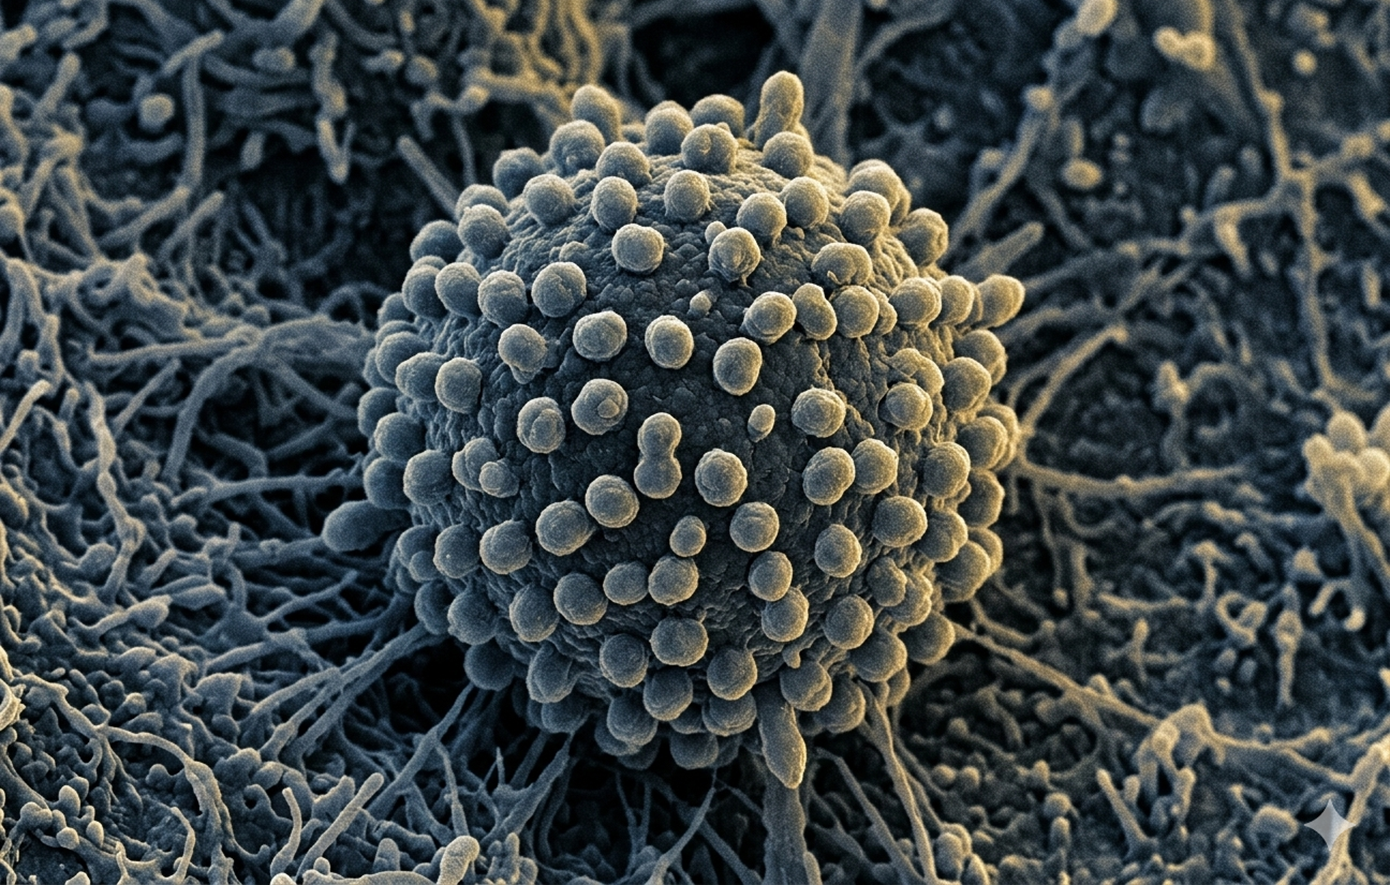

Το όνομα «κορονοϊός» προέρχεται από την Λατινική λέξη «corona», που σημαίνει «στέμμα», την οποία δανείζεται από την ελληνική λέξη «κορώνη». Πρώτοι απέδωσαν το όνομα η Τζουν Αλμέιντα και ο Ντέιβιντ Τάιρελ οι οποίοι παρατήρησαν και μελέτησαν για πρώτη φορά τους ανθρώπινους κορονοϊούς.

Η λέξη χρησιμοποιήθηκε για πρώτη φορά το 1968 από μία άτυπη ομάδα ιολόγων στο περιοδικό Nature για να αναφέρουν μία καινούργια οικογένεια ιών. Το όνομα τους αποδόθηκε από την χαρακτηριστική όψη τους στο ηλεκτρονικό μικροσκόπιο όπου διακρίνονται ετα χαρακτηριστικά ξογκώματα γύρω από την επιφάνειά τους που θυμίζουν στέμμα.